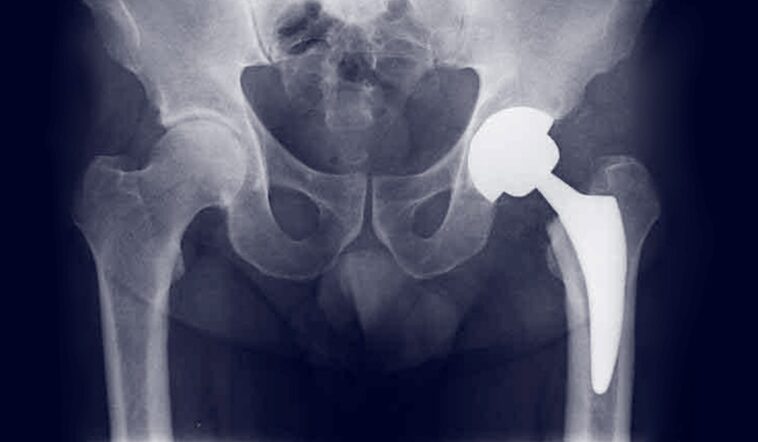

La protesi d’anca è una sostituzione chirurgica dell’articolazione dell’anca, composta da una cupola acetabolare (che sostituisce la parte del bacino) e da uno stelo femorale con una testina sferica, che sostituisce la testa del femore. Viene impiantata per eliminare il dolore, ripristinare la mobilità e migliorare la qualità della vita.

Tradizionalmente, l’intervento prevedeva un’incisione ampia e il distacco di numerosi muscoli. Oggi, invece, si ricorre sempre più spesso alla tecnica mini invasiva.

La protesi anca mini invasiva è una variante più moderna e meno traumatica della chirurgia tradizionale. Grazie a incisioni più piccole (di circa 7-10 cm) e all’utilizzo di strumenti specifici, si evita il distacco dei muscoli principali, riducendo il trauma chirurgico. Questo comporta numerosi vantaggi: